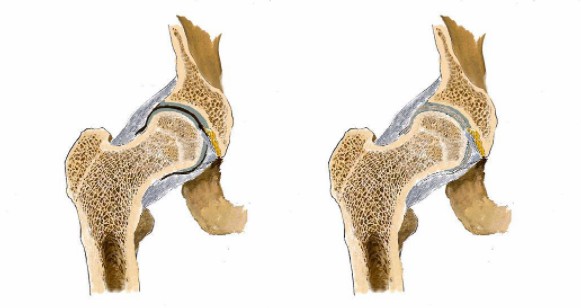

“強(qiáng)直性脊柱炎”是男孩在檢查單上看到的字眼,他知道醫(yī)生想通過檢查確定自己是否得了這個病。

“無法根治”“病后期致殘”“失去自理能力”……一個個關(guān)鍵詞出現(xiàn)在詞條上,男孩有些許目眩,明明只是腿疼怎么就變成了這樣?

男孩繼續(xù)搜索,“強(qiáng)直性脊柱炎會死嗎?”,詞條出現(xiàn)了“不死癌癥”。

看男孩不說話,醫(yī)生繼續(xù)說道:“你的HLA-B27顯示陰性,如果是陽性就可以確診是強(qiáng)直性脊柱炎,現(xiàn)在只能排查……如果確診是強(qiáng)直性脊柱炎,就要就要及早治療,因?yàn)檫@個病是不可逆的,我們只能延緩它病程進(jìn)度……”